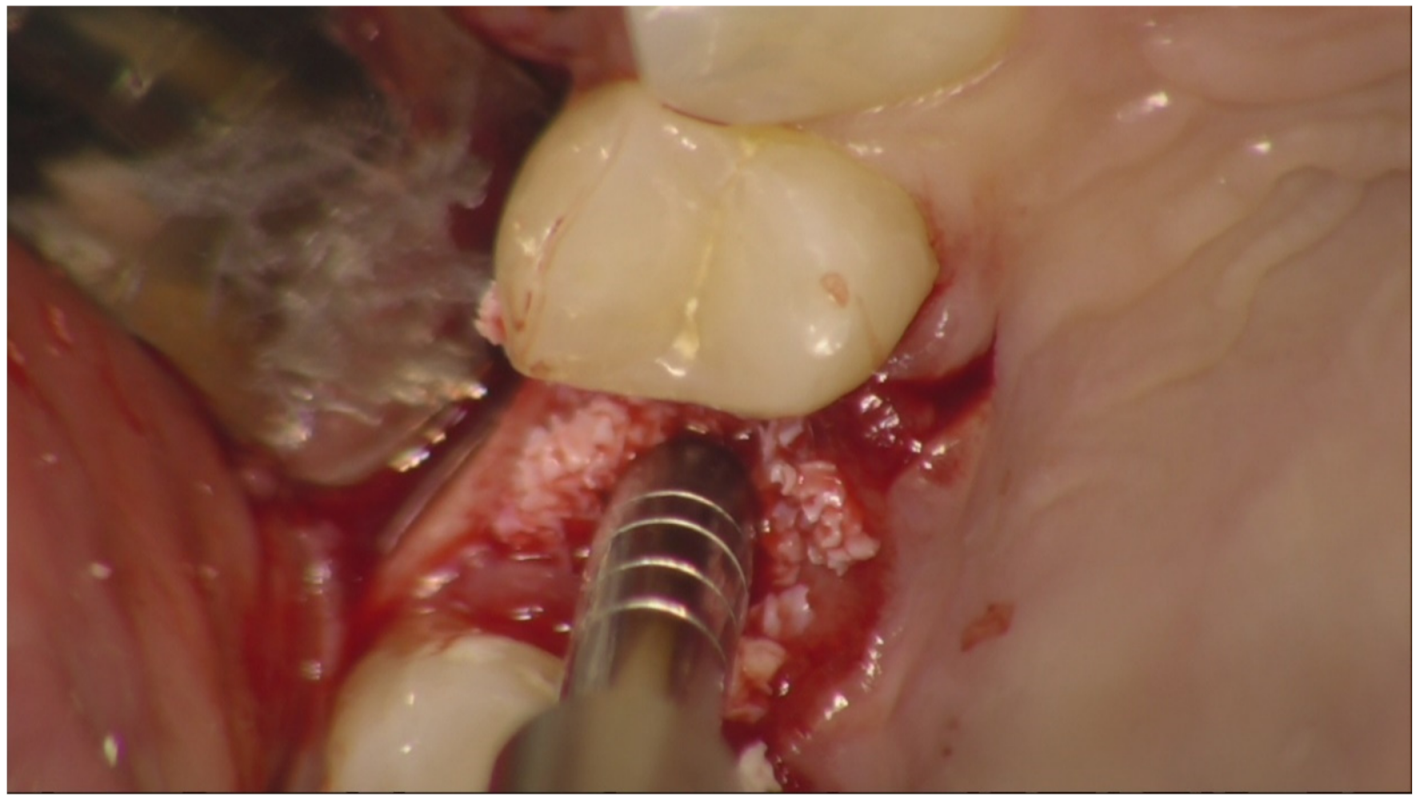

Before surgery, all patients underwent professional oral hygiene with periodontal treatment and supportive therapy, if needed. At the end of the prevention phase, the patients were moved to a careful home and professional oral-hygiene maintenance. Radiographic examination, including periapical radiographs (Figure 1), and computer tomography or CBCT scans, were also performed. All the implants were placed according to a predefined protocol, which includes antibiotic prophylaxis with amoxicillin clavulanate 1 gr every 12 h for six days, starting from the day of the surgery, following by a rinse with 0.2% chlorhexidine (CHX) solution for 1 min. Local anesthesia was performed with a 4% solution of articaine with epinephrine 1:100,000. All the implants were inserted after crestal and intrasulcular incisions performed to raise a mucoperiosteal flap. All the implants were 4.3 mm of diameter (Nobel Replace CC PMC Tapered, Nobel Biocare, Zurich, Switzerland), with 0.75 mm of machined collar. The implant sites were prepared using the lance drill of 1.5 mm of diameter to sign the implant position. Then the twist drill of 2 mm of diameter was used to reach the sinus floor cortex with a drill stop positioned 0.5 mm below the maxillary sinus floor (working length), estimated by using the CT or CBCT scan. Finally, the narrow platform drill (made for 3.5 mm diameter implants, Figure 2) was used at the working length to underprepare the implant recipient site. A collagen matrix (Condress, Smith and Nephew, Agrate Brianza, Italy) was inserted in the prepared site and then the sinus floor was fractured with a calibrated osteotome of 3.5 mm of diameter (Nobel Biocare). At this point, graft material consisting of 0.5 g. of deproteinized anorganic bovine bone, in small microgranules of 0.25–1 mm (Bio-Oss, Geistlich Pharma, Switzerland), mixed with sterile saline, was compacted into the sinus using the same osteotome, up to the working length (Figure 3). At the end of this procedure, all the implants were inserted according to a one-stage protocol [28,29], reaching a primary implant stability from 30 to 50 Ncm. All the implants were 8 to 10 mm of length (Figure 4), depending of the residual bone height. After implant placement, all the patients received oral and written recommendations about the correct maintenance, oral hygiene (i.e., mouthwash 0.2 CHX solutions twice a day, no brushing implant areas), and soft diet. Patients were also instructed to avoid any increase of the intrasinus pressure. The postoperative analgesic treatment was performed with ibuprofen 600 mg, as needed, but a maximum every eight hours for two to three days after the intervention. About two weeks after surgery, sutures were removed.

Figure 2.

Recipient bed after drill preparation. Occlusal view.